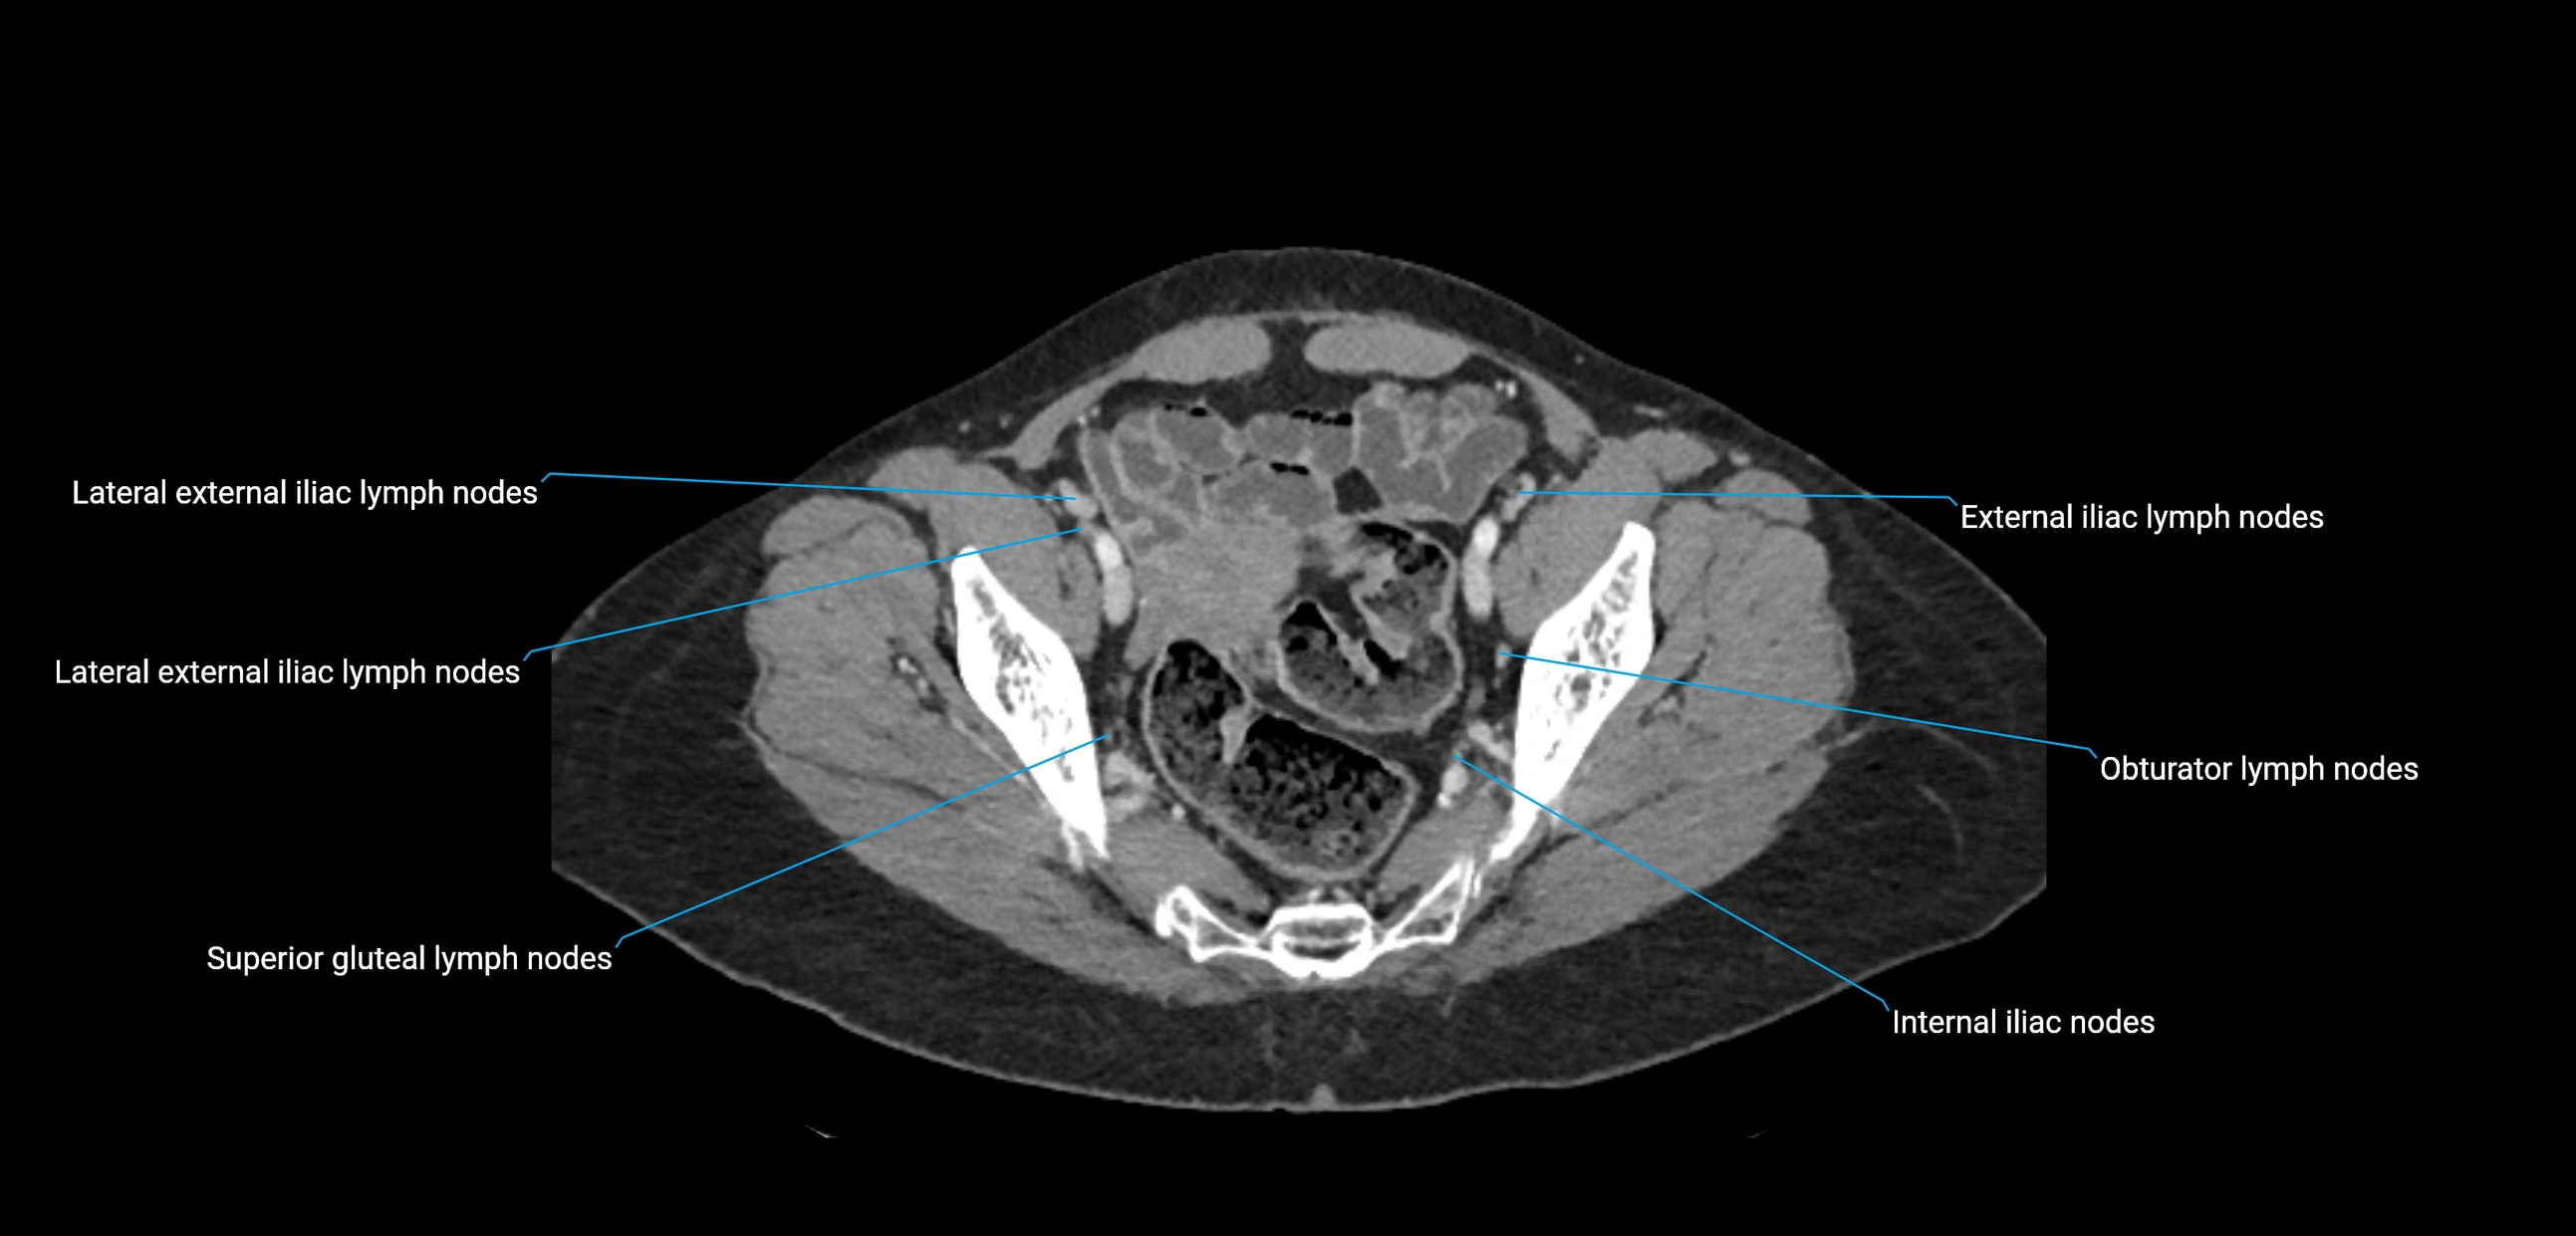

CT image

image